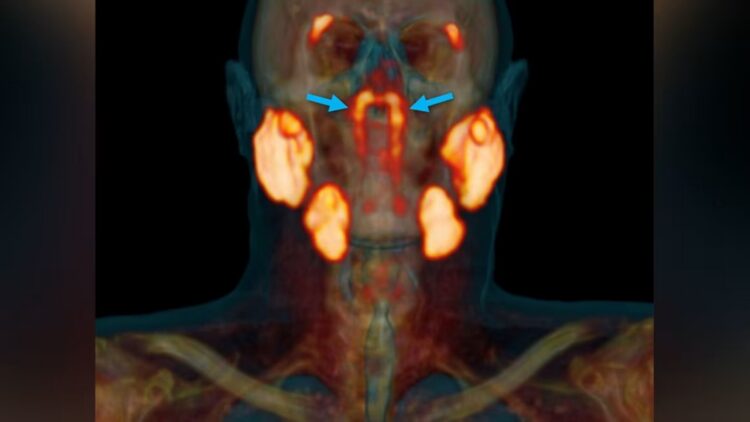

We usually though that we knew everything about human body… But now, a group of Dutch researchers has found what appears to be a new human organ (yes!) in the throat, a pair of glands located right at the junction between the nasal cavity and the pharynx. They have been named tubarial glands and everything indicates that they could have an important role in saliva production. The finding not only forces us to rethink anatomy as we knew it, it also opens the door to improving treatments against head and neck cancer.

The discovery happened almost by chance, which is incredible! While tests were being carried out on patients with prostate cancer, specialists used an advanced imaging technique called PSMA PET/CT. Unlike magnetic resonance or ultrasound, this method showed in great detail some unknown structures in the nasopharynx.

After reviewing the results, the scientists confirmed that it was not a misinterpretation: what they were seeing was a real anatomical entity. The hypothesis is that these glands help produce saliva, although broader studies are still needed to know their function with certainty.